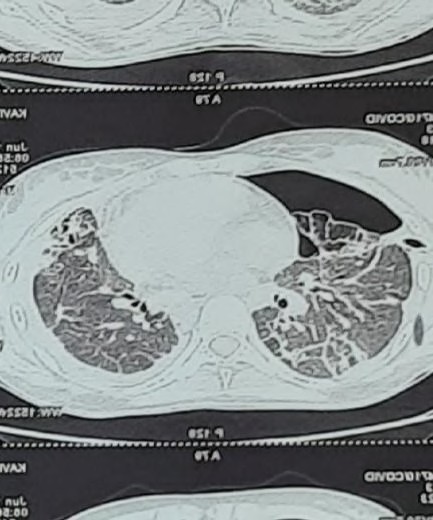

Fig. 6: Reverse halo sign or atoll sign

Present study out of 107 cases 106 cases had abnormal HRCT findings out of which 99(92.5%) had bilateral abnormality and 7(6.5%) had unilateral abnormality and 7 had normal HRCT finding. Similar finding observed in [9] showed out of total of 175 chest CT scans were scored in this study. A total of 140 (80%) chest CT scans demonstrated bilateral infiltrates, and 31 (18%) chest CT scans showed unilateral infiltrates, whereas 4 (2%) chest CT scans had no abnormal findings. In our study, according to HRCT findings, GGO was seen in 70(65.4%) cases, consolidation in 34(31.8%), atelectatic band in 1(0.9%), crazy paving in 5(4.7%) cases, reticulation in 11(10.3%) cases, Peripheral hyperdensity in 9(8.4%), mediastinal LN and lymphadenopathy 2(1.9%) cases respectively, 1(0.9%) case with COPD, ground glass haziness, emphysematous changes, mild Fibrosis and septal thickening respectively. Similar findings observed in Sudhir Bhandari et al.119. (2020) showed that in an early phase of disease (10 d), among radiologically positive patients (8 out of 15) 12.50% patients had GGO, 75.00% patients had both GGO and consolidation, while remaining 12.50% patients had only consolidation in imaging of HRCT chest.